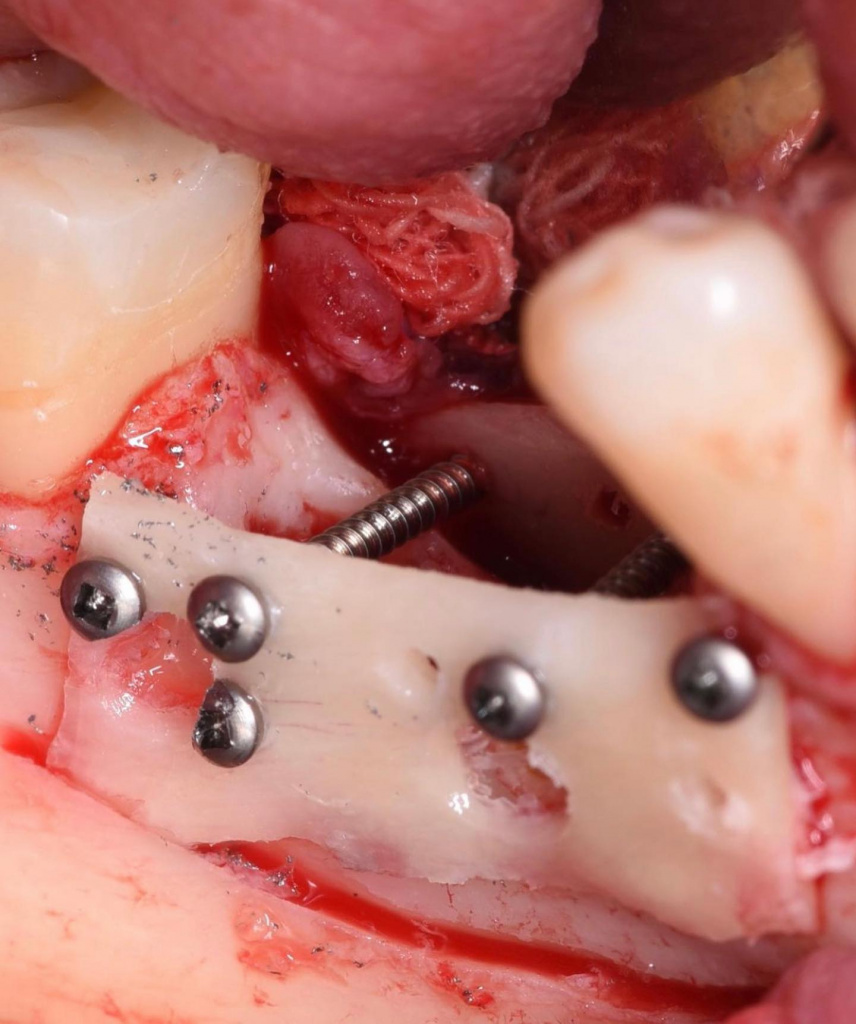

- Забор блоков для костной пластики с косой линии нижней челюсти

- Фиксация блоков

- Установка имплантатов AnyRidge

- Заполнение пространства между блоками аутостружкой, смесью ауто- и алло-материалов